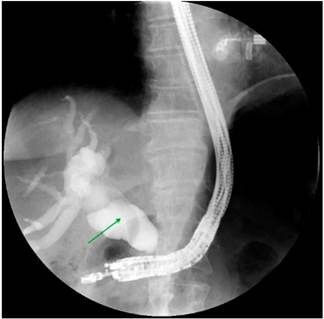

Based on these findings, palliative care was decided by performing a biliary stent placement by means of an ERCP. During the procedure, the papilla was found to be distorted with local retraction of the duodenal walls, and despite cannulation of the distal bile duct was achieved, cannulation of the proximal bile duct was unsuccessful. EUS-guided biliodigestive shunt was then performed, in which a neoplastic infiltration of the duodenal papilla preventing its cannulation and a 23 mm heterogeneous hypoechoic lesion in the head of the pancreas with an up to 18 mm retrograde bile duct dilation were found (Figure 4). An initial puncture of the mass was performed for histological study purposes and then of the transduodenal bile duct with a 19 Fr. needle, which allowed the advancement of the 0.035” hydrophilic guide wire; dilatation was achieved using a biliary balloon dilator under fluoroscopic control and subsequent placement of the 10 x 80 mm fully covered metal stent was performed, which was released under endoscopic and fluoroscopic control achieving adequate opening and drainage of the contrast medium and clear bile, without subsequent complications (Figures 5 and 6). The cytology report of the samples obtained through endosonography confirmed adenocarcinoma involvement. Two months later, a total bilirubin control was performed obtaining the following results: total bilirubin: 2.42 mg/dL; direct bilirubin: 1.85 mg/dL, and indirect bilirubin: 0.58 mg/dL (Figure 7). Palliative care was continued in the oncology service.

Figure 5 Endoscopic-guided bile duct cannulation and fluoroscopy in which dilatation with distal amputation is observed.